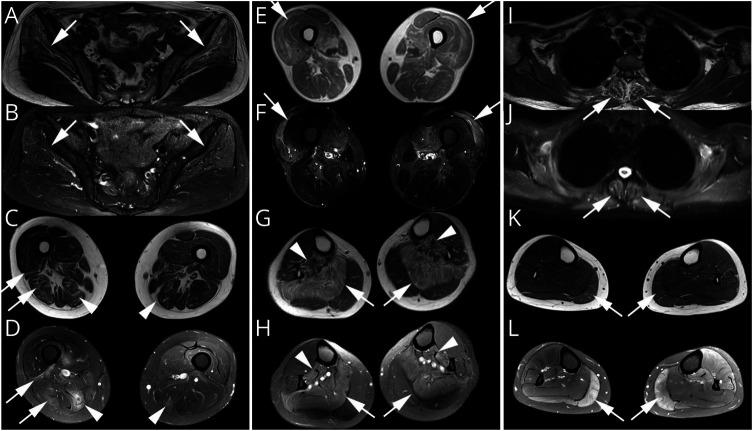

Most of the patients exhibited asymmetric limb muscles weakness (71%, 12/17) and neck extensor weakness (53%, 9/17). Immunofixation electrophoresis was performed in 11 patients, and 4 of them were identified with monoclonal gammopathy of undetermined significance (MGUS). EMG from 16 patients demonstrated a myopathic pattern with spontaneous activities in 69% (11/16) of them. Muscle MRI showed preferential involvement of paraspinal, gluteus minimus and medius, semimembranosus, and soleus muscles. Suspected nemaline bodies on modified Gomori trichrome were confirmed by IHC using anti-α-actinin antibody (100%, 17/17), anti-myotilin antibody (94%, 16/17), anti-desmin antibody (94%, 16/17), anti-α-B crystallin antibody (65%, 11/17), and anti-telethonin antibody (18%, 3/17) with various positive rates. Notably, anti-α-actinin IHC showed the highest percentage of strongly positive staining (77%, 13/17), being the only one without negative results. Moderate improvement following autologous stem cell transplantation (ASCT) was noted in 3/4 patients with MGUS; favorable outcomes were also achieved in 6/7 patients without MGUS, including 3 patients with complete recovery who were given a combined treatment of prednisone and another immunosuppressant.

大多数患者表现为不对称性肢体肌肉无力(71%,12/17)和颈部伸肌无力(53%,9/17)。11 例患者进行了免疫固定电泳,其中 4 例被确定为意义未明的单克隆丙种球蛋白血症(MGUS)。16 例患者的肌电图显示肌病模式,其中 69%(11/16)有自发性活动。肌肉 MRI 显示脊柱旁、臀小肌和中肌、半膜肌和比目鱼肌优先受累。改良 Gomori 三色染色上可疑的杆状体用抗α-肌动蛋白抗体(100%,17/17)、抗肌球蛋白抗体(94%,16/17)、抗结蛋白抗体(94%,16/17)、抗α-B 晶体蛋白抗体(65%,11/17)和抗 telethonin 抗体(18%,3/17)进行免疫组化确认,阳性率各不相同。值得注意的是,抗α-肌动蛋白 IHC 显示出最高比例的强阳性染色(77%,13/17),是唯一没有阴性结果的染色。4 例 MGUS 患者中有 3 例接受自体干细胞移植(ASCT)后有中度改善;7 例无 MGUS 患者中也取得了良好的结果,包括 3 例完全恢复的患者,他们接受了泼尼松和另一种免疫抑制剂的联合治疗。